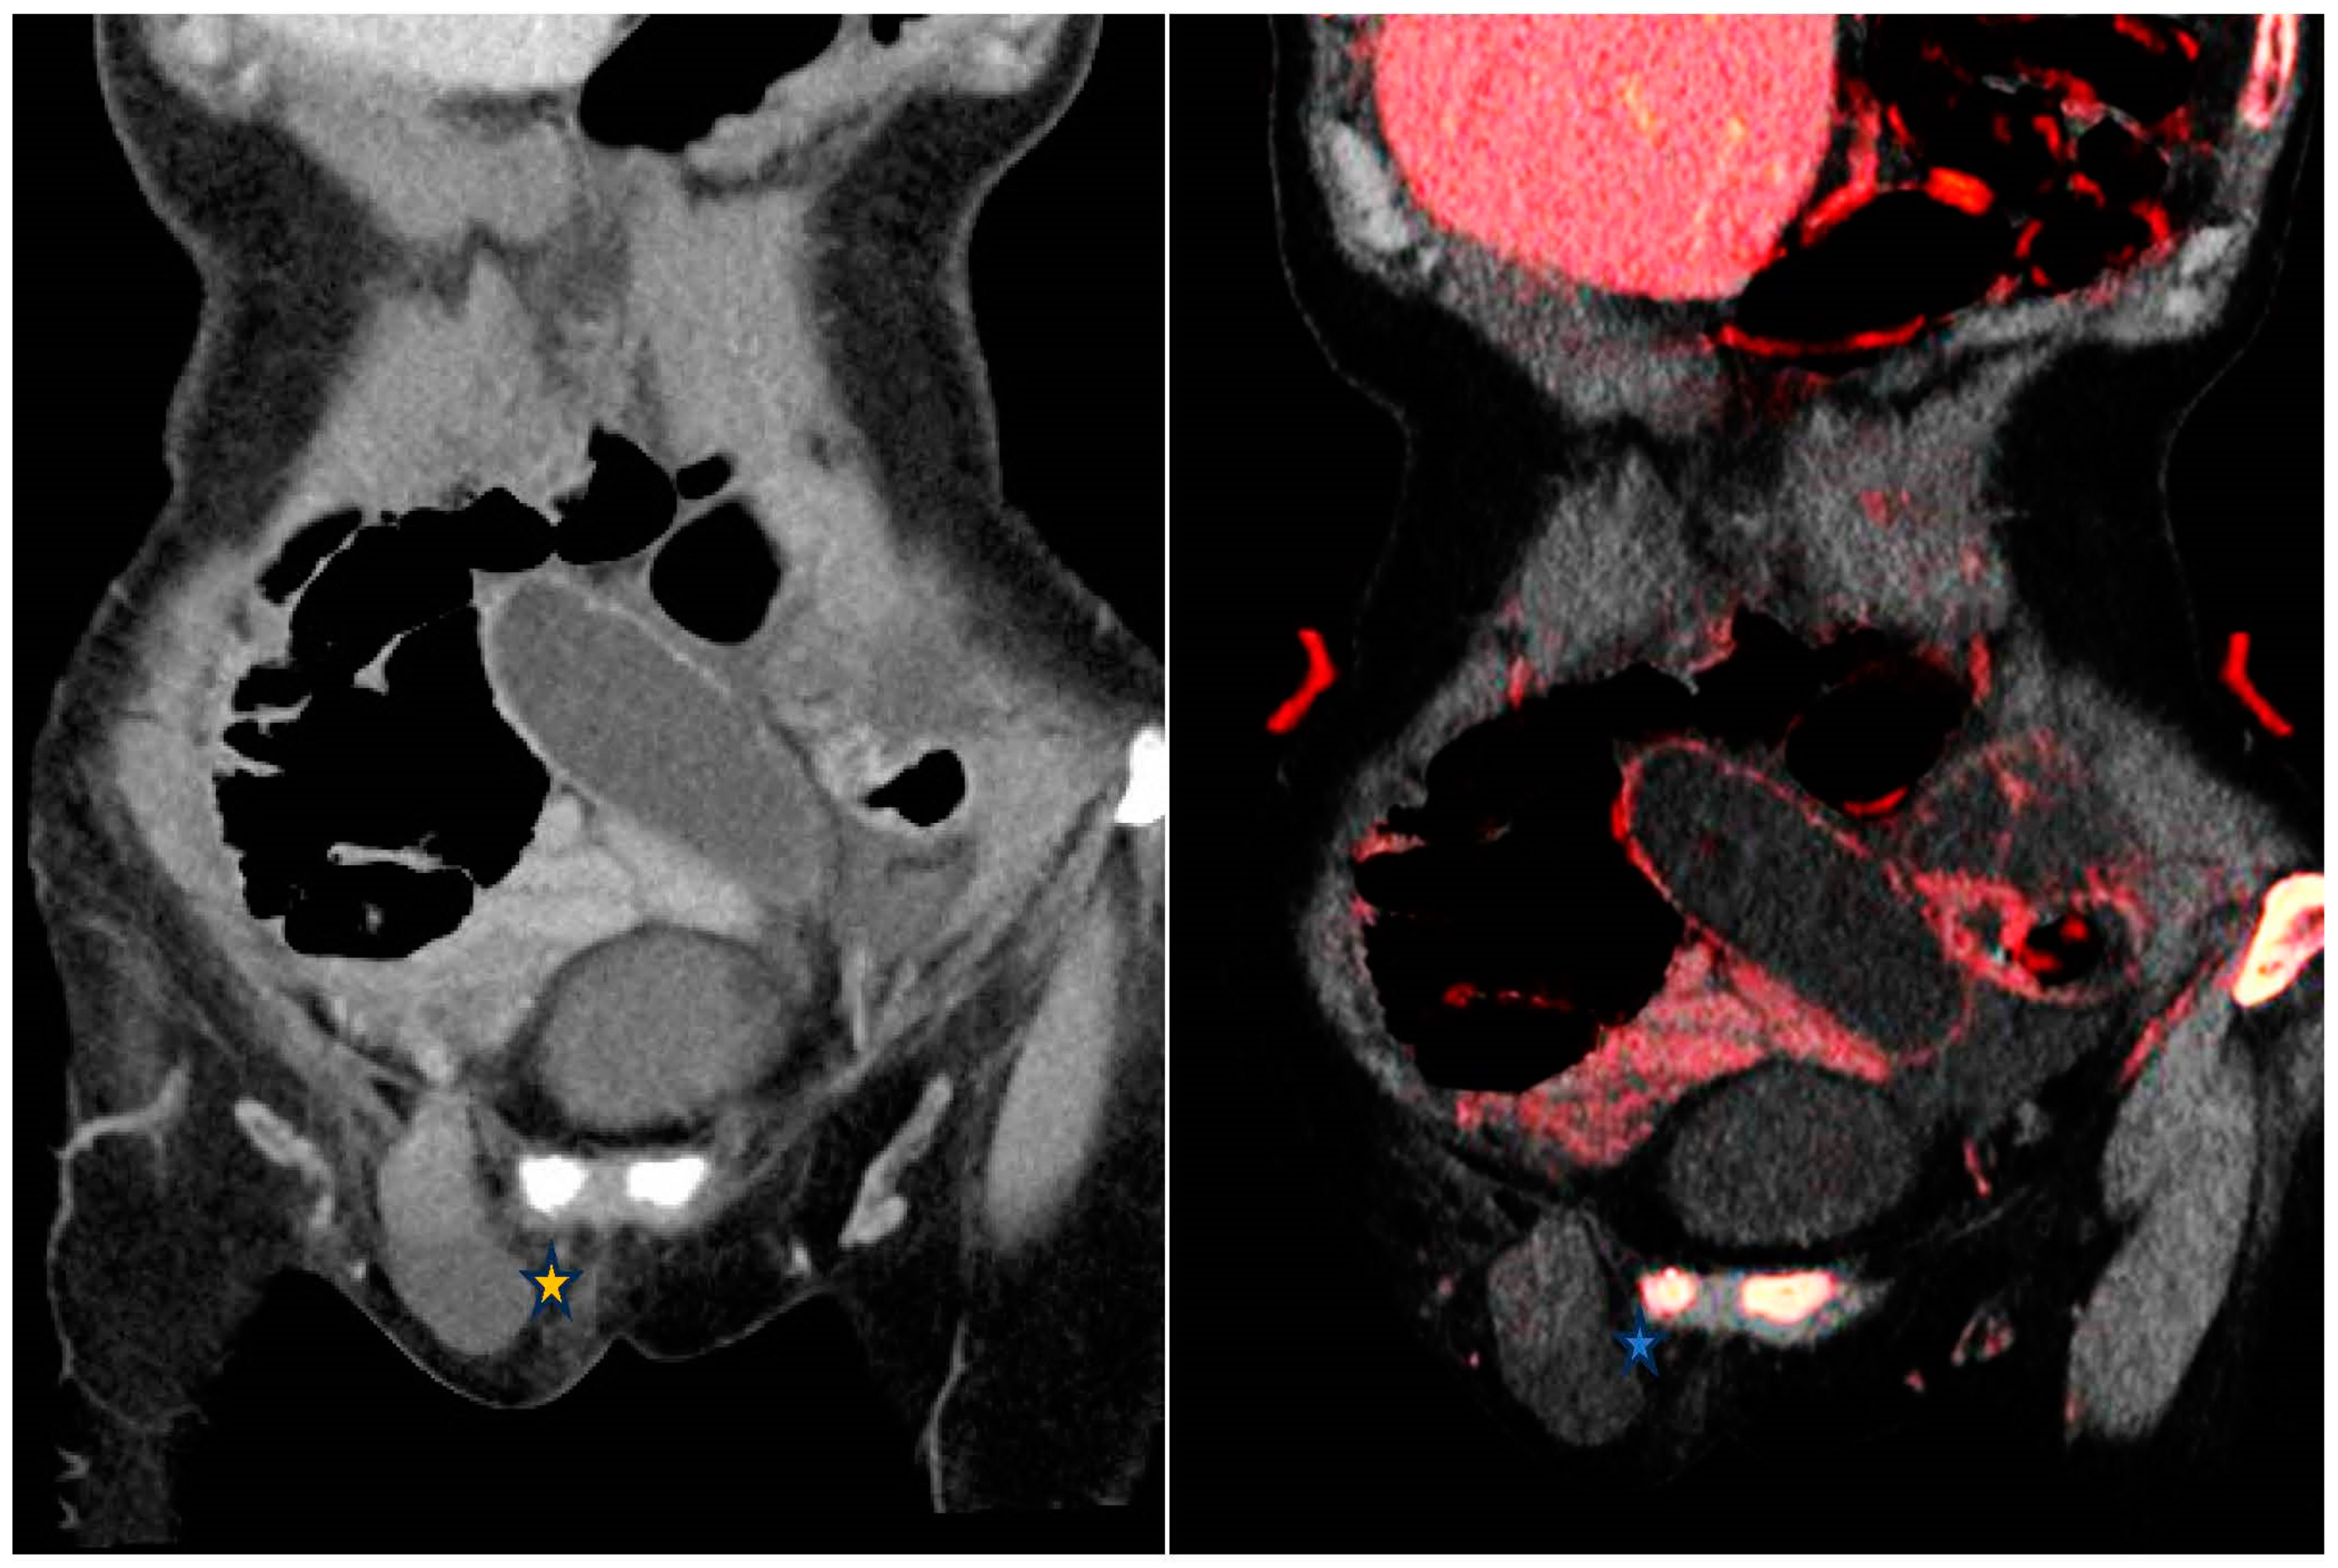

Dual-energy CT 原理を理解し臨床で活用する Dual-energy CT 原理を理解し臨床で活用する | 粟井 和夫 |本の詳細情報

Dual-energy CT 原理を理解し臨床で活用する | 粟井 和夫 |本。Dual-energy CT 原理を理解し臨床で活用する | 粟井 和夫 |本。Dual-energy CT 原理を理解し臨床で活用する | 粟井 和夫 |本。

Dual Energy CT – Radiology@Home

Dual-energyCT原理を理解し臨床で活用する

メジカルビュー社

粟井和夫

2019/09/29

4758316120

9784758316125

Dual-energy CT 原理を理解し臨床で活用する

良い

Dual Energy CT – Radiology@Home

Dual-energyCT原理を理解し臨床で活用する

メジカルビュー社

粟井和夫

2019/09/29

4758316120

9784758316125

Dual-energy CT 原理を理解し臨床で活用する

良い